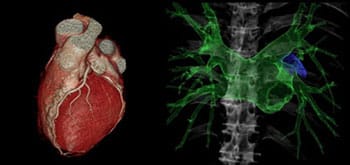

0.27秒の高速回転により、従来の心臓CTでは検査が困難であった不整脈、高心拍、心拍変動の症例にも対応して撮影することができます。

256スライスによるワイドエリア化により、全身を約3秒程度で撮影することができます。高速スキャンと高画質を両立するとともに、患者さまの息止め時間が大幅に短くなります。手術前の検査では、手術支援画像としてさまざまな3次元画像を作成することで、形態の把握や手術計画に利用しています。

この検査は体幹部のがんの病巣発見や転移巣の検索、化学療法や放射線治療によるがんの治療効果判定などに用いることができ、簡易的にPET検査のような画像を撮像できることから非常に注目されている検査の一つです。特徴として、放射線被ばくがないので繰り返し検査ができ、造影剤や放射性医薬品の注射をする必要がありません。検査時間は30分程度で、検査費用はPET検査の6分の1程度で負担が少ない検査です。